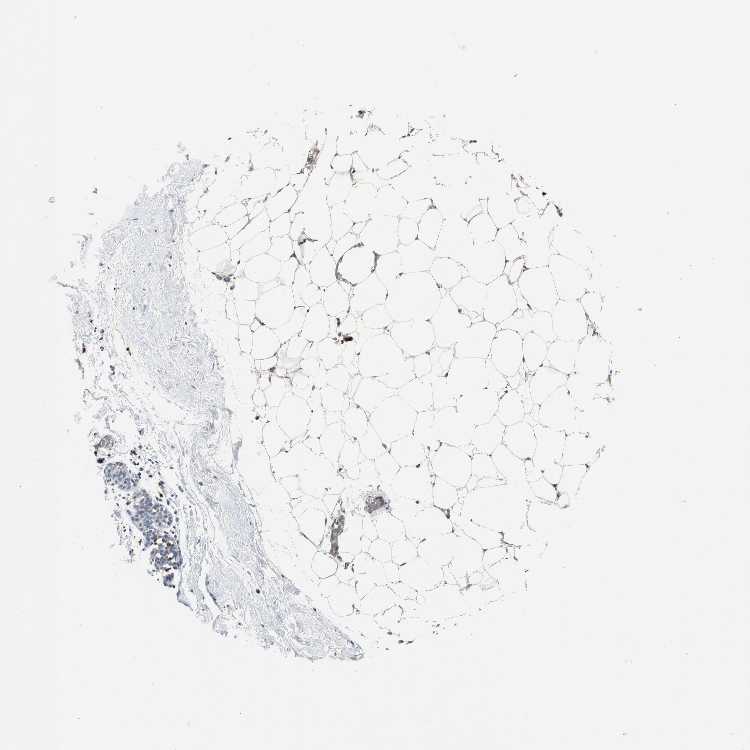

BREAST - Antibody stainingi

Antibody staining in the annotated cell types in the current human tissue is reported as not detected, low, medium, or high, based on conventional immunohistochemistry profiling in selected tissues. This score is based on the combination of the staining intensity and fraction of stained cells.

Each image is clickable and will lead to virtual microscopy that enables deeper exploration of all samples and also displays staining intensity scores, fraction scores and subcellular localization as well as patient and tissue information for each sample.

Antibody HPA002327Antibody HPA006040Antibody CAB022160

Adipocytes -LowNot detected

Glandular cells Not detectedLowNot detected

Myoepithelial cells Not detectedNot detectedNot detected